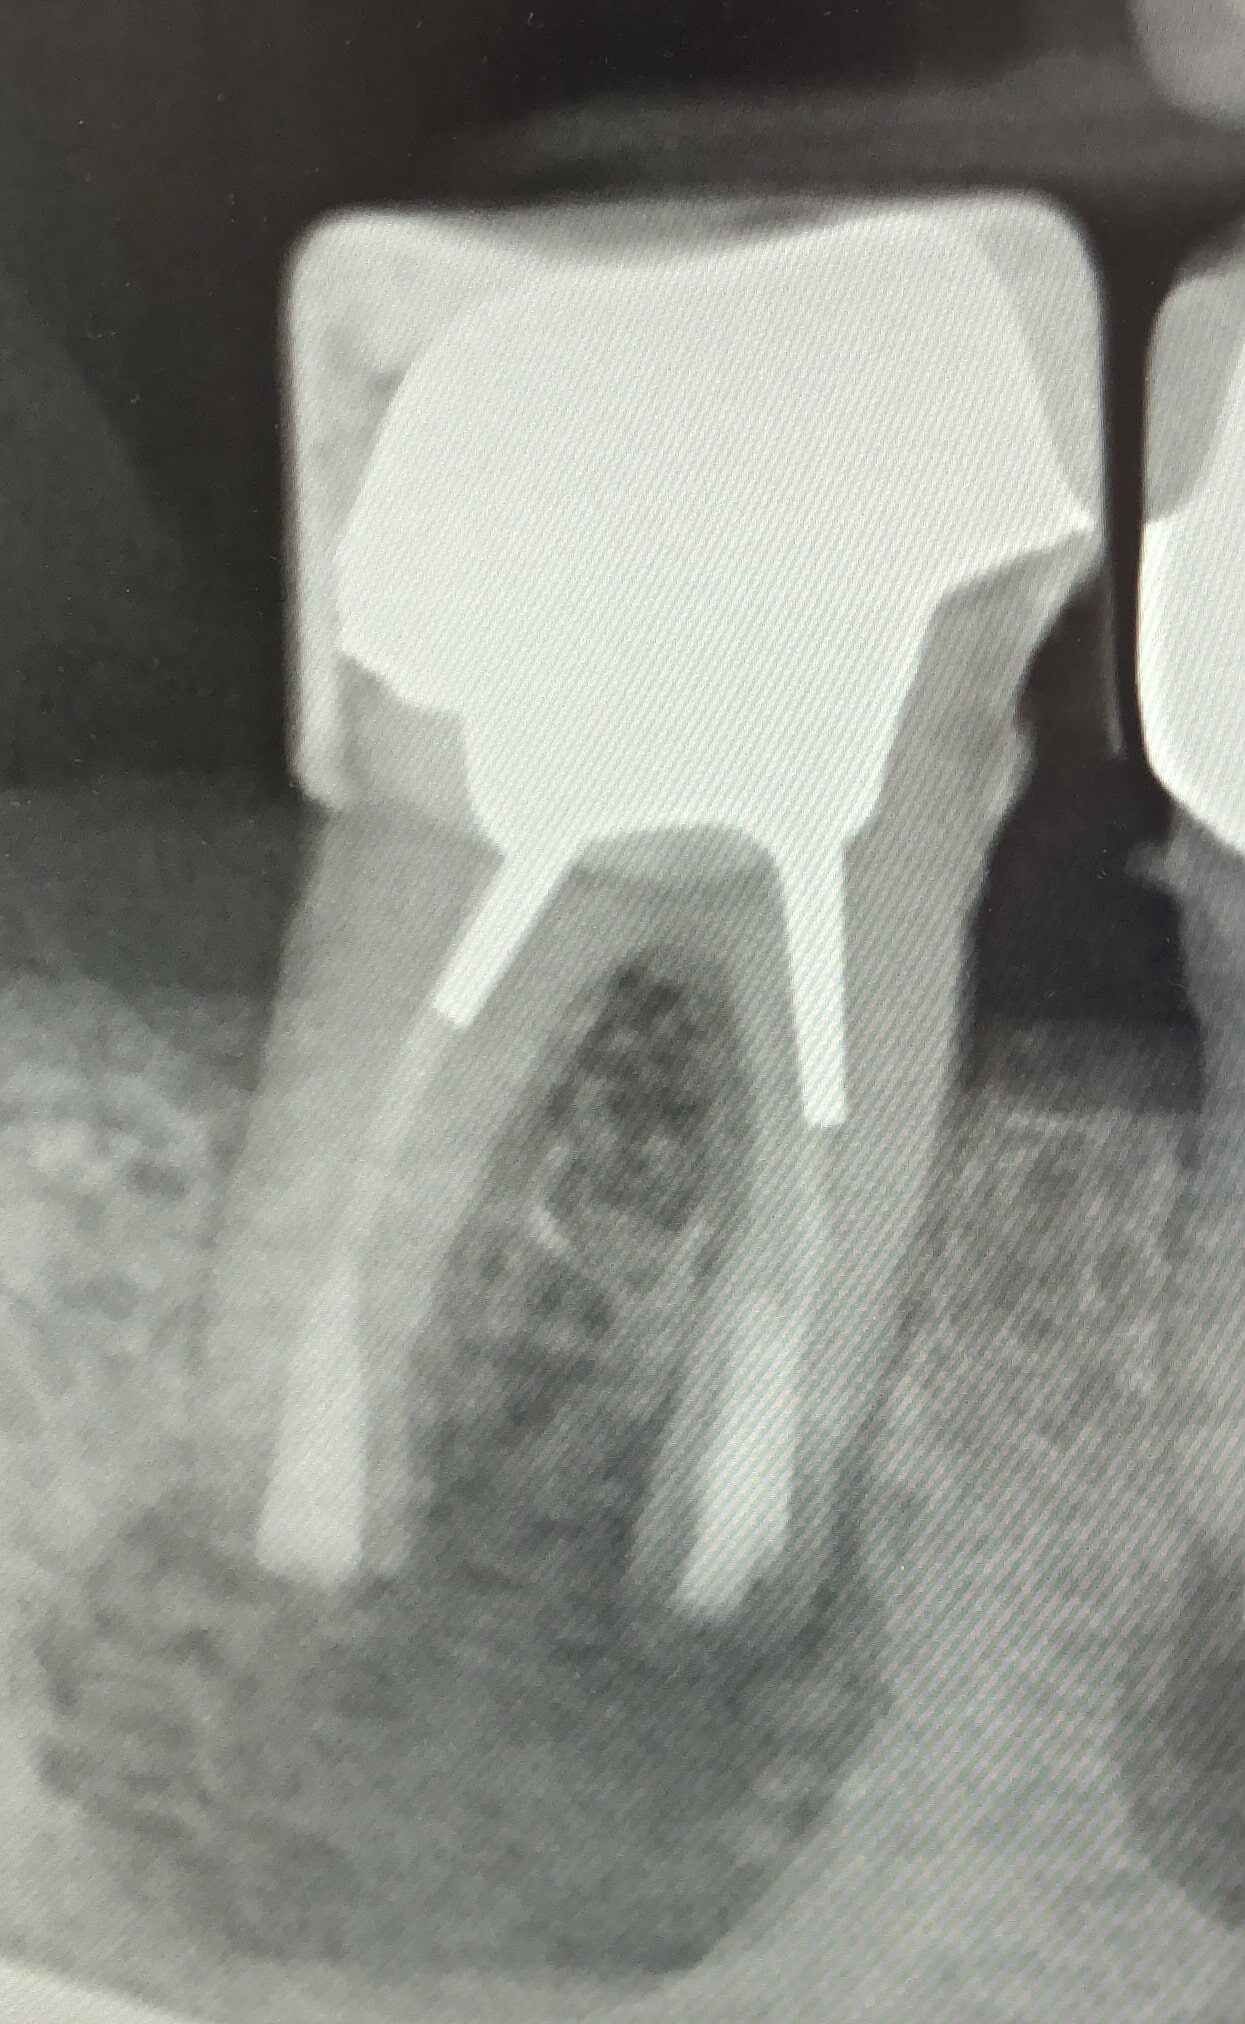

Röntgenaufnahme zweier ungehandelter Zähne mit Wurzelkanal Problemen. Die Aufnahmen zeigen die Zahnwurzeln und die umgebende Knochensubstanz.

Vorher